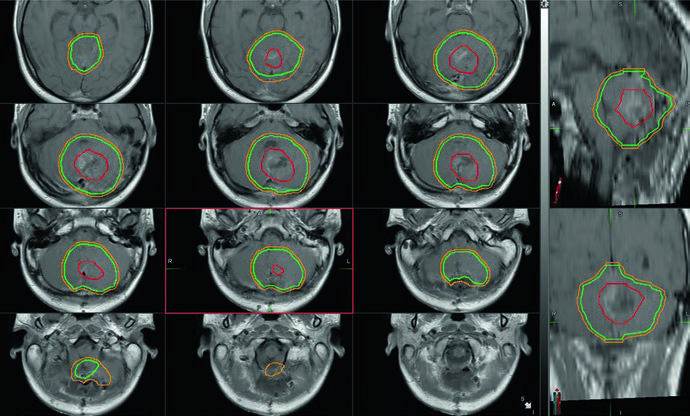

Ependimoma: delineación y márgenes de CTV

Al igual que en el meduloblastoma, la delineación volumétrica basada en TC es obligatoria. Todos los pacientes requieren RM pre y posoperatoria de alta calidad con cortes de 1–3 mm de cerebro y columna total. La diseminación por LCR es menos frecuente que en el meduloblastoma — inferior al 10% al diagnóstico — pero debe descartarse mediante RM espinal y citología del LCR.

La extensión de la resección es el factor pronóstico más importante. Si la RM posoperatoria muestra enfermedad residual, debe considerarse la re-resección cuando la morbilidad anticipada sea aceptable.

El GTV consiste en la cavidad de resección posoperatoria con atención especial a los forámenes de Luschka y Magendie, frecuentemente comprometidos. Consultar al neurocirujano aporta valor para identificar hallazgos intraoperatorios no evidentes en la imagen.

Los márgenes de GTV a CTV han disminuido durante la última década. El protocolo ACNS 0831 del COG trató con CTV = GTV + 0,5 cm hasta una dosis total de 54 Gy en 30 fracciones. Para minimizar la toxicidad del tronco cerebral, la expansión del CTV en el tronco se limitó a 3 mm. Un conedown adicional hasta 59,4 Gy (para niños mayores de 18 meses) excluye completamente el tronco cerebral, el quiasma óptico y la médula cervical del volumen de boost.

Volúmenes recomendados para ependimoma infratentorial

| Volumen | Definición |

|---|---|

| GTV | Lecho tumoral con enfermedad residual y paredes de la cavidad en RM. Atención especial a los forámenes de Magendie y Luschka. |

| CTV54 | GTV + 5 a 10 mm restringido por hueso y tentorio. No debe extenderse en el tronco cerebral más de 3 mm. |

| CTV59,4 | GTV + 5 mm excluyendo completamente tronco cerebral, quiasma óptico y médula cervical. |

| PTV | CTV + 3 a 5 mm. Se acepta subdosificación del PTV en regiones donde sea necesario respetar la tolerancia de la médula cervical y el quiasma óptico. |

Fuente: Target Volume Delineation and Field Setup, 2nd Edition (Table 34.4)

Muchos radiooncólogos pediátricos aún prefieren márgenes más amplios (CTV = GTV + 1 cm) con dosis total de 54 Gy fuera de protocolo, y este abordaje se considera aceptable. El protocolo ACNS 0831 estableció como objetivo que la D10% de la médula cervical no supere 57 Gy, y durante el tratamiento del PTV59,4, el volumen total de la médula espinal no debe recibir más del 70% — o 126 cGy por fracción — durante cada una de las últimas tres sesiones.

Cuando se trata hasta 59,4 Gy, se recomienda un abordaje en dos fases: el conedown a 54 Gy permite preservar dosis adicional en tronco cerebral, quiasma óptico y médula cervical. Independientemente de la extensión inferior del tumor, el PTV54 no debe extenderse por debajo del foramen magno.